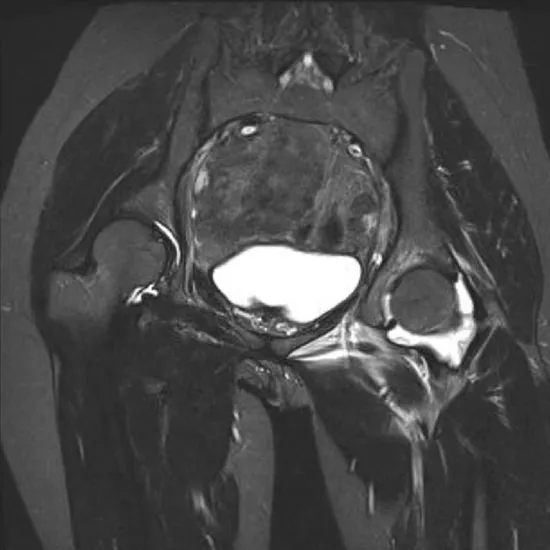

MRI of the left hip joint is a non-invasive imaging technique to identify the causes of unexplained hip pain, resulting in limited mobility and limping. These conditions include tumours, infection of the hip joint, inflammation or degeneration of the tendons surrounding the hip joint, sports injuries, trauma, and cancer suspicion.

MRI (Magnetic Resonance Imaging) screening of the Left Hip Joint is a non-invasive radiology test used to evaluate the condition of the Left Hip Joint and surrounding tissue. MRI Left Hip Joint is done to look for Left Hip Joint conditions and the surrounding area.